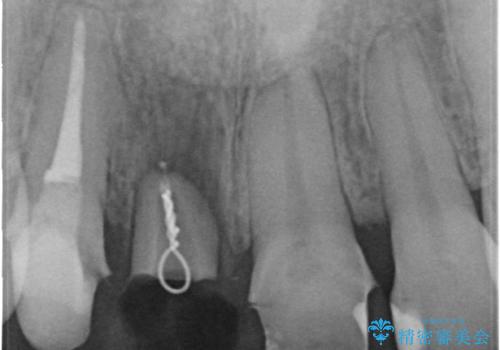

古いかぶせ物は土台ごと歯から脱落してしまっており、歯の内面には複数の亀裂が入っている状態でした。残存歯質が非箔であることと、動揺の程度から、やむを得ず抜歯→ブリッジという方法を選択していただき、歯根挺出を用いることでなるべく前歯の骨の陥没を防ぎ、ブリッジを製作しました。

- 抜歯前提の歯根挺出により保存の難しい前歯を抜去

→根管治療のやり直しなどを経て、ブリッジを製作する。